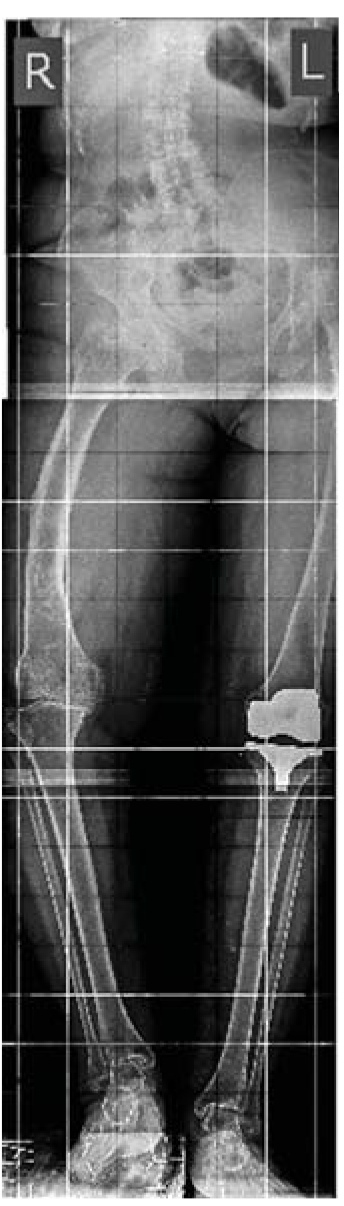

Пациентка А., 56 лет, поступила в клинику ФГБУ «РНИИТО им. Р.Р. Вредена» (далее РНИИТО) 21.04.2017 с диагнозом: консолидированный с варусной и торсионной посттравматической деформацией (перелом диафиза в средней трети) правой бедренной кости посттравматический гонартроз III стадии, болевой синдром, фиброзный анкилоз правого коленного сустава, укорочение правой нижней конечности 5 см (рис. 1). Пациентка была направлена в РНИИТО из региона Российской Федерации для госпитализации с целью получения высокотехнологичной медицинской хирургической помощи.

Рис. 1. Телерентгенограммы обеих нижних конечностей пациентки до операции.

Fig. 1. Long leg films of both lower extremities of the patient before the surgery.

По телерентгенограммам обеих нижних конечностей и рентгенограммам коленного сустава были оценены характер и величина имеющейся деформации правой нижней конечности во фронтальной и сагиттальной плоскостях (23° варусной деформации, 9° антекурвационной деформации). Были зарегистрированы изменения, характерные для посттравматического гонартроза III стадии с преимущественным поражением медиального отдела коленного сустава: значительное сужение суставной щели (по типу «кость на кость»), выраженные костные разрастания по краю мыщелков бедренной и большеберцовой костей, латеральный подвывих голени, признаки пателлофеморального артроза. По данным компьютерной томографии была выявлена наружная торсия бедренной кости 15° на уровне консолидированного с деформацией перелома. По результатам лабораторных исследований признаков системного воспаления у пациентки не было обнаружено.

С помощью телерентгенограмм нижних конечностей пациентки разработано предоперационное планирование и были изготовлены индивидуальный интрамедуллярный стержень MetaDiaFix-F 11×620 мм и блокирующие винты 6,0 мм к нему.